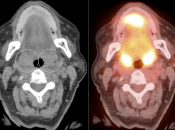

- NON-ENLARGED AND:

- Unilaterally Avid (≥ Liver Uptake)

- OR

- Uptake “Unquestionably” > Contralateral Tonsil

We typically report, “While this uptake is typically physiologic or inflammatory in nature, direct visualization may be of diagnostic value, if clinically warranted.”

(If the uptake is < liver uptake, we presume the metabolic activity to be physiologic or inflammatory)

- UNILATERALLY ENLARGED AND:

We typically report, “While its increased size and increased metabolic activity may be inflammatory in nature, direct visualization may be warranted to exclude a neoplastic process in this case.”

- Any Unilateral Tonsillar Uptake Associated with Hypermetabolic Cervical Nodes:

Clearly, the presence of hypermetabolic cervical nodes dramatically increases the likelihood of malignancy (and the confidence of your reporting).